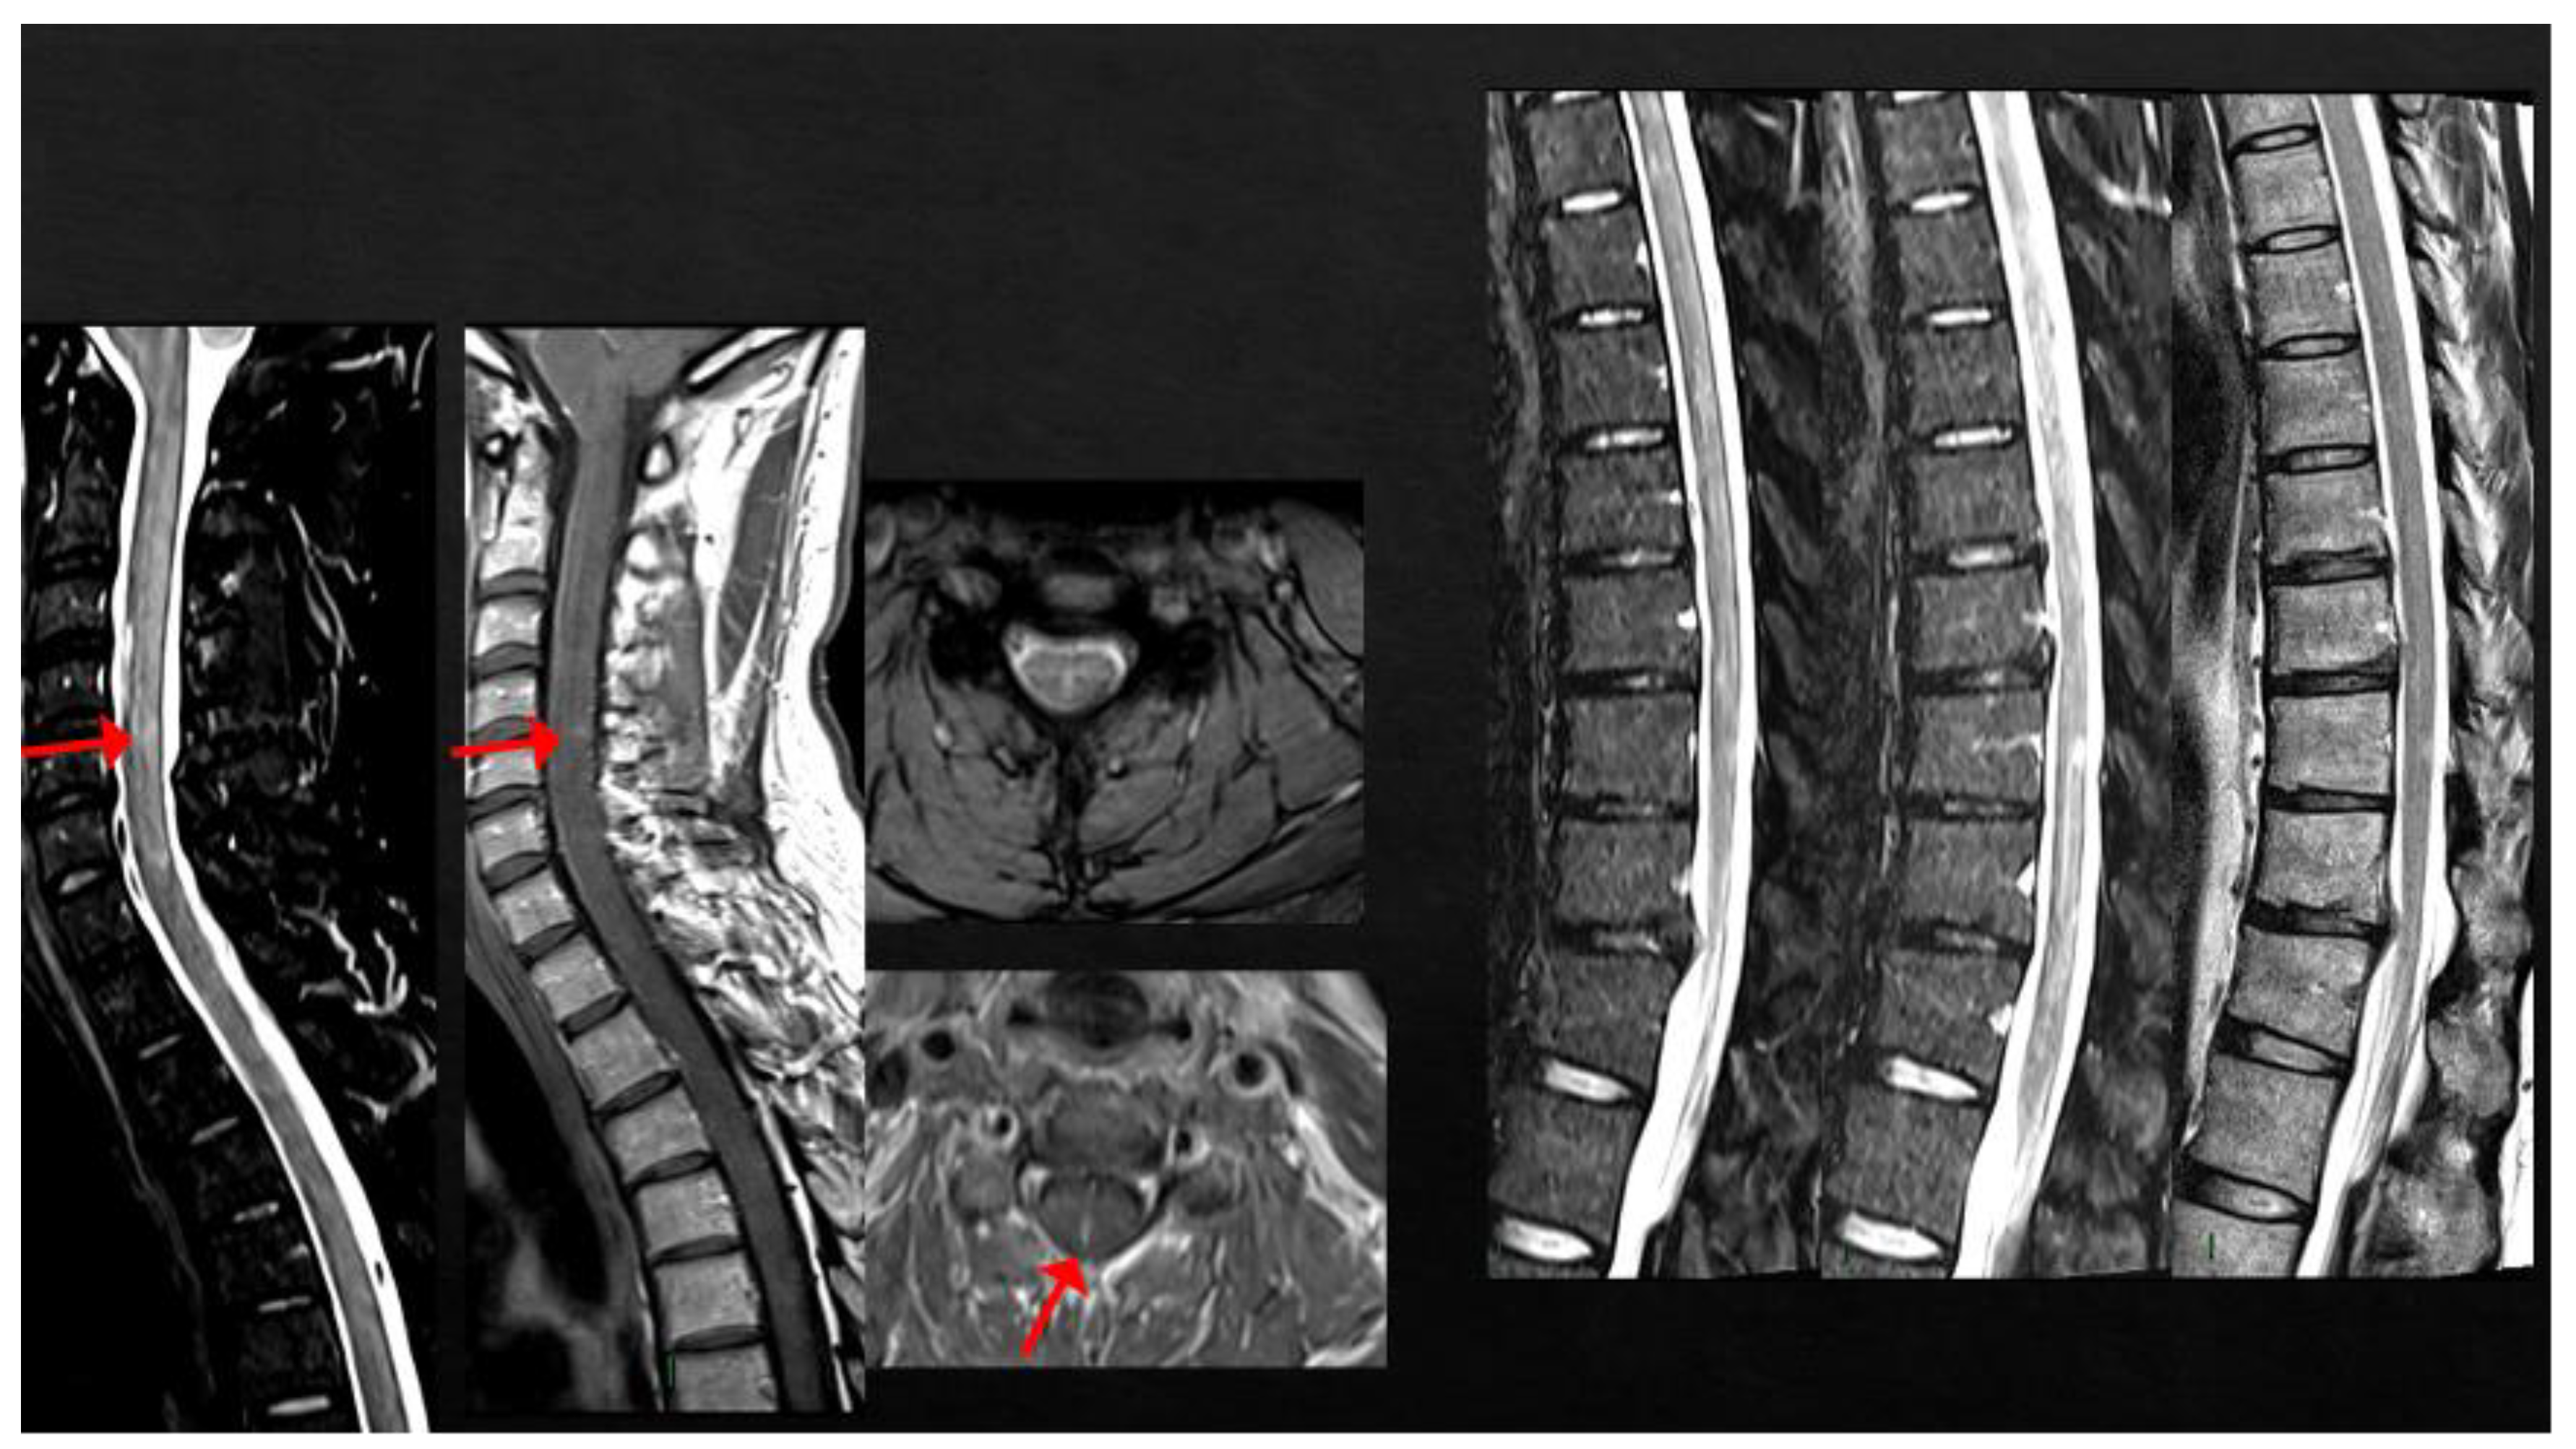

4. MS Onset after Vaccine Exposure

5. MS Relapses after Vaccine Exposure

| Case 6 | BNT/2nd | 2 weeks | Multisymptomatic (gait/trunk ataxia, sphincter) | (MRI not in acute phase) | + | + | -/- | |

| Case 7 | ChAdOx1/1st | 1 week | SC | + | - | + | -/- | |

| Case 11 | BNT/1st | 1 week | SC | SC | + | + | NA | |

| Case 12 | BNT/1st | 2 weeks | SC | SC | + | + | +/+ | |

| Lee et al. [51] * | Various | 0–55 days | Mainly SC | Various sites | variable | various | +/+ | |

| Czarnowksa et al. [62] | JJ/1st | 2 weeks | SC | Brain, SC | + | + | +/+ | |

| Havla et al. [95] | BNT/1st | 1 week | SC | SC | + | + | +/+ | |

| Khayat-Khoei et al. [64] 3 cases | mRNA vaccines/ 2nd (2) | 2–3 weeks | ON (2) SC (1) | Brain (1) SC (2) | + | NA | -/+ | |

| Kaulen et al. [65] | BNT (4) | 2 weeks | ON (4) SC (2) ST (2) | ON (4) SC (2) ST (2) | + | +/+ | ||

| Mele et al. [66] | Mod/1st | 2 days | Cerebellum | ST | + | + | −/+ | |

| Rinaldi et al. [68] 2 cases | BNT/1st (1) 2nd (1) | 1 week | BS+SC (1) ST (1) | BS+SC (1) ST+ SC non-ce (1) | + | + | +/+ | |

| Gernert et al. [63] 5 cases | BNT (4, 3 cases 1st, 1 case 2nd), 1 ChadoOx/2nd | 1–2 weeks | ON (2) BS (1) SC (1) BS+SC (1) | SC (2) BS/cerebellum (3) | + | +/+ | ||

| $ Watad et al. [69] 4 cases | BNT/1st (2) Mod/2nd (2) | 1 day–1 month | ST (1); cerebellum, SC (1) SC (2) | + | + | + | +/+ | |

| $ Nistri et al. [67] 2 cases | ChadOx/1st | 1 week | ON (2) IT (1) | + supratentorial | + | + | -/- | |

| Toljan et al. [70] 4 cases | BNT/1st (2) | Uncertain | + | + | + | -/- | ||

| MS RELAPSE | ||||||||

| Rinaldi et al. [68] | BNT/1st | 2 weeks | Cerebellum/BS | ST | + | + | IFNb | NA |

| $ Al-Midfai et al. [71] | JJ/2nd | 2 weeks | Uncertain (unilateral motor deficit) | - | + | NA | - | NA |

| $ Maniscalco et al. [72] | BNT/1st | 2 days | Unilateral SM deficit | ST | + | NA | FTY | NA |

| Kataria et al. [73] | BNT/2nd | 3 weeks | ON + SC | ST | + | - | IFNß | NA |

| Seyed Ahadi et al. [74] | Sinopharm/1st | 2 days | Paraparesis and ataxia | BS | + | NA | - | NA |

| Kayat-Khoei et al. [64] 4 cases | mRNA vaccines 1st (1) and 2nd (3) | 1–3 weeks | ON (2) BS+SC (1) Possibly SC (1) | Brain (3) | + (new SC in 2 cases) | NA | NTZ (1) FTY (1) None (2) | NA |

| $ Nistri et al. [67] 14 cases | ChadOx/1st (2) mRNA/1st (7), 2nd (5) | 2 days–3 weeks | BS/cerebellum (4) SC (6) Possibly SC (6) | Brain (13) | + | + | + (9) - (5) | NA |

| D’apolito et al. [75] | BNT/2nd | 4 days | BS/cerebellum | + | - | + | FTY | NA |

| $ Fragoso et al. [49] 8 cases | BNT/1st | BS | Various | Some | NA | NA | Various DMT (7) | NA |